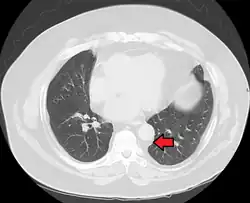

Mediastinal lipomatosis | |